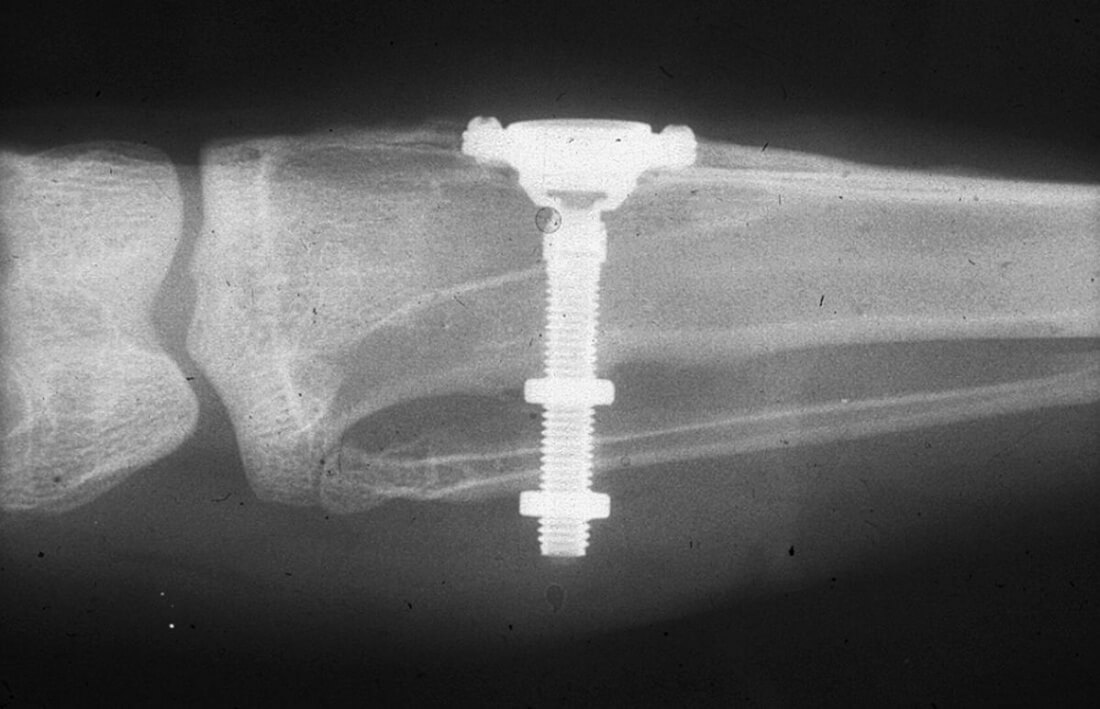

Мы сделали рентгеновские контрольные снимки —  панорамный для оценки положения имплантатов и прицельный для контроля посадки абатментов.

На последнем видно, что абатменты (особенно правого на фото зуба) не сели на свои места, между ними и платформами имплантатов есть щель — и эта ситуация наглядно демонстрирует, ПОЧЕМУ такие снимки необходимы. Мы вернули пациентку в хирургический кабинет и провели коррекцию абатмента (уменьшили ширину трансгингивальной части), После чего, проводили пациентку в кабинет стоматолога-ортопеда для временного протезирования.

После фиксации временных коронок мы делаем прицельный контрольный снимок для контроля посадки абатментов на платформу и оценки качества изготовления композитных реставраций.